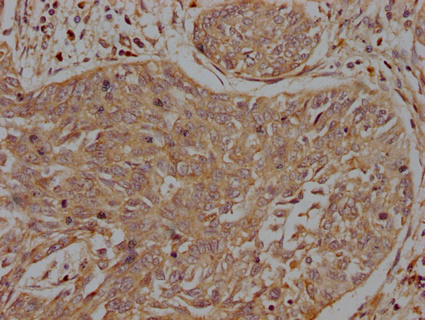

IHC image of CSB-PA011755LA01HU diluted at 1:200 and staining in paraffin-embedded human cervical cancer performed on a Leica BondTM system. After dewaxing and hydration, antigen retrieval was mediated by high pressure in a citrate buffer (pH 6.0). Section was blocked with 10% normal goat serum 30min at RT. Then primary antibody (1% BSA) was incubated at 4°C overnight. The primary is detected by a biotinylated secondary antibody and visualized using an HRP conjugated SP system.

IHC image of CSB-PA011755LA01HU diluted at 1:200 and staining in paraffin-embedded human kidney tissue performed on a Leica BondTM system. After dewaxing and hydration, antigen retrieval was mediated by high pressure in a citrate buffer (pH 6.0). Section was blocked with 10% normal goat serum 30min at RT. Then primary antibody (1% BSA) was incubated at 4°C overnight. The primary is detected by a biotinylated secondary antibody and visualized using an HRP conjugated SP system.